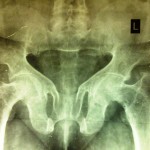

Image Quiz Feb 2014

What’s the Diagnosis? Please Note: DO NOT REPLY BY EMAIL . Instead Use the POLLS on the website or the COMMENT Section Popular answer does not imply right answer. Right answer will be published by the end of the month